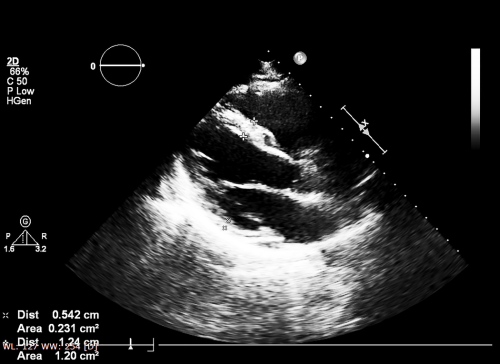

2.基本計測の実際

1.心機能計測のポイントと注意点